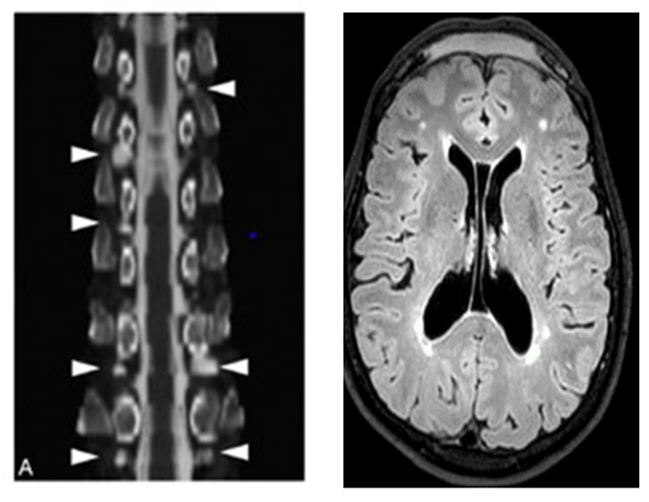

Repeated MRI showed regression of meningeal thickening, a right frontal encephalocele, and multiple thoracolumbar radicular cysts. Spinal imaging with contrast revealed small epidural leaks at L4-L5 and L3-L4 levels (Figure 2).

Figure 2: Multiple radicular cysts at the dorsal and lumbar level. Protrusion of the frontal lobe at the level of the crista galli on the right corresponding to a right encephalocele.